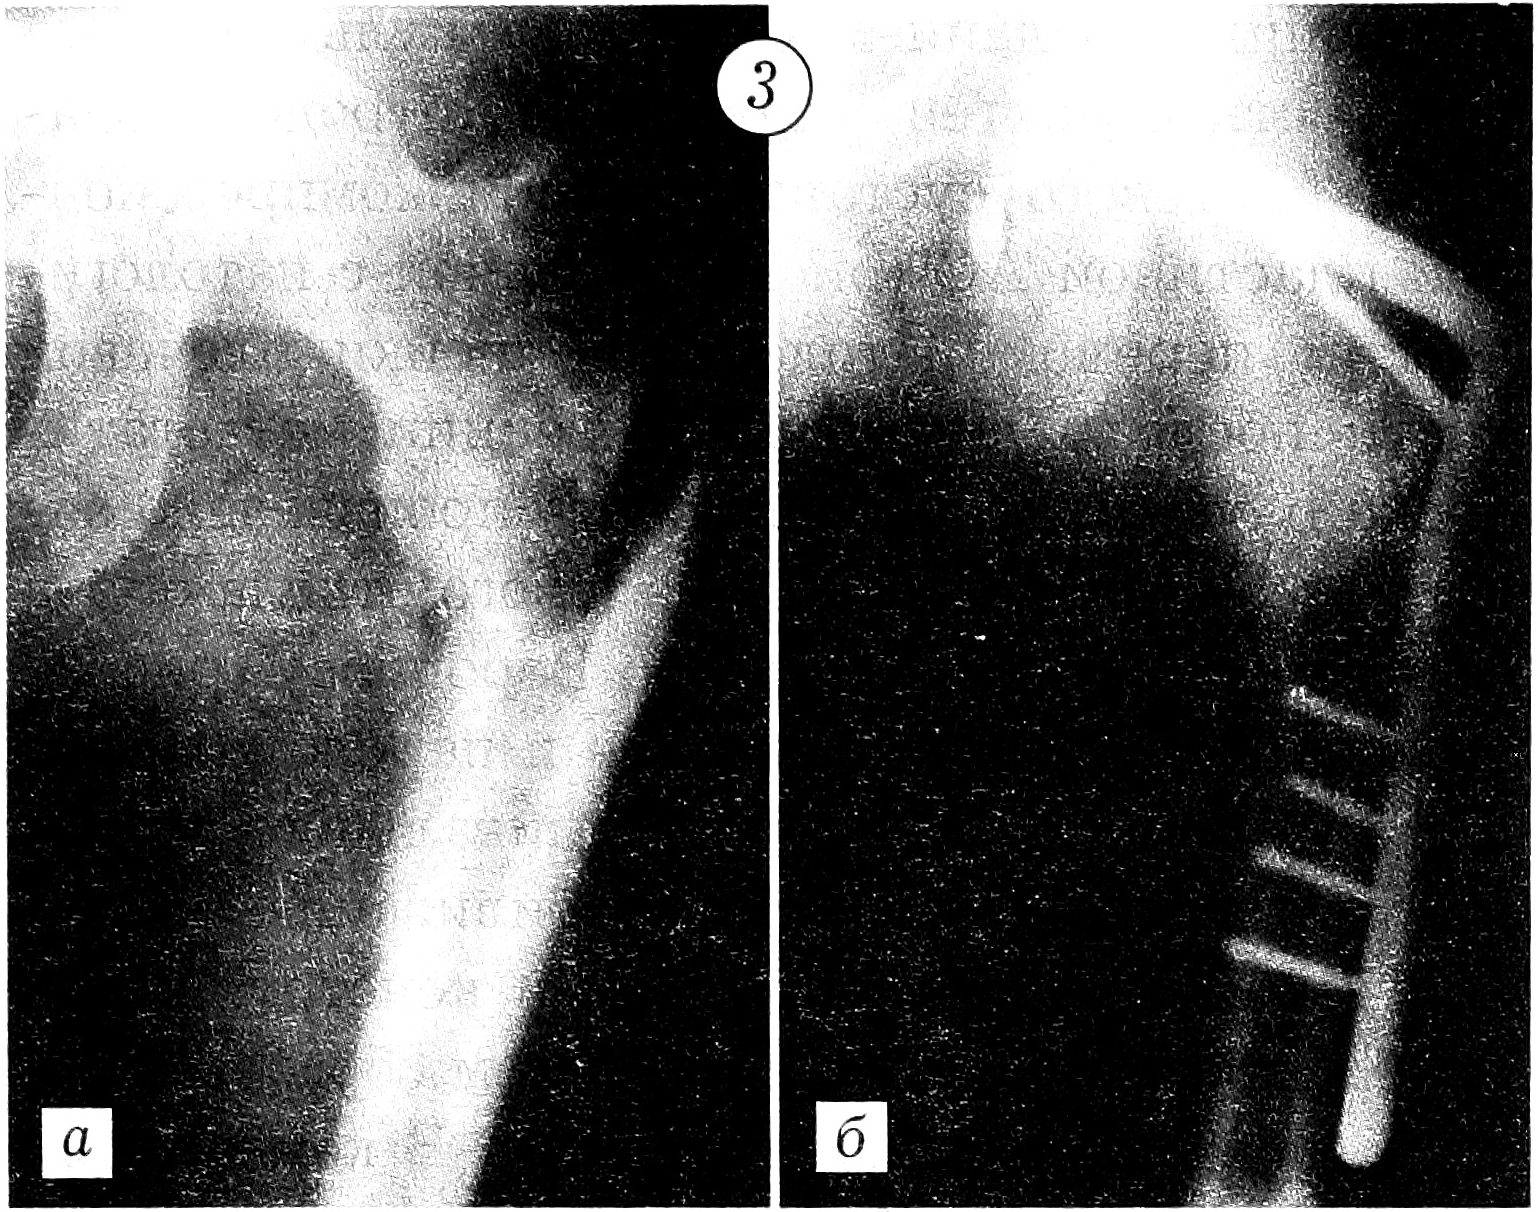

Фиксация отломков выполнялась по методике АО с применением металлоконструкций в комбинации с заполнением костного дефекта цементом [3, 5, 6]. Больной с обширным остеолитическим поражением проксимального отдела бедра произведено эндопротезирование. Поскольку ацетабулярный компонент тазобедренного сустава не был вовлечен в опухолевый процесс, выбран метод тотального эндопротезирования по Вирабову. Такая тактика снижает риск развития нестабильности сустава и необходимость повторных реконструктивных операций. При переломе диафиза плечевой кости отломки были фиксированы аппаратом Илизарова. У больного с патологическим переломом лучевой кости на фоне деструктивного остеолитического поражения, захватывающего ее дистальные 2/3, выполнена резекция патологического очага с последующим созданием синостоза культей лучевой кости с локтевой костью и артродезированием кистевого сустава длинной компрессионной пластиной АО (рис. 1). Больной с патологическим переломом головки и шейки плечевой кости после радикальной резекции метастатического остеолитического очага произведено эндопротезирование проксимального отдела плеча протезом из акрилоксида по Воронцову (рис. 2). При подвертельном переломе и переломах диафиза и шейки бедра после радикального удаления метастаза выполняли стабилизацию отломков Г-образными пластинами и конструкциями DHS с последующим заполнением образовавшегося дефекта костным цементом. В комбинации с компонентами стабилизирующих конструкций костный цемент повышает прочность фиксации (рис. 3 и 4).

Рис. 3. Рентгенограммы левой бедренной кости больного с переломом диафиза бедра в области метастаза меланомы глаза. a — до операции; б — после остеосинтеза Г-образной пластиной.